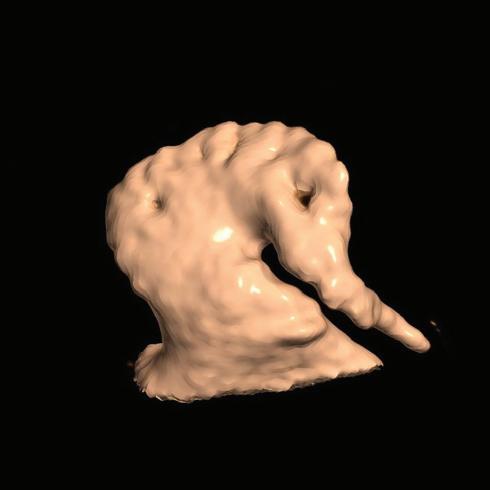

Figure 7: Assessing Elimination of Arrhythmogenic Fibrotic Substrate by Late Gadolinium Enhancement-MRI

Against this background, we have recently analysed the potential role of LGE-MRI to assess the long-term effect of VT ablation in terms of arrhythmogenic substrate elimination (unpublished data). Three to 6 months following the procedure, effective ablation was reflected by pronounced reduction of LGE-MRI-detected border zone scar volume and extent of slow conduction channels compared to the preprocedural LGEMRI (Figure 7). In patients undergoing repeat ablation procedures, this arrhythmogenic substrate elimination as determined by LGE-MRI correlated well with EAM. Thus, LGE-MRI-based lesion assessment may be of potential value to evaluate the efficacy of ventricular substrate ablation and to predict VT recurrences and clinical outcome. However, as mentioned above, clinical validation is warranted.

Left panel: LGE map of the left ventricle prior to substrate-based ventricular tachycardia ablation. LGE depicts an antero-apical scar. A 3D-analysis using the ADAS 3D software predicts a slow-conduction channel (black line) extending over 30 % of the transmurality that was confirmed by invasive electroanatomical mapping. Right panel: LGE map of the left ventricle 3 months post-ventricular tachycardia ablation. LGE indicates complete scar homogenisation and ‘dechannelling’ with ablation lesions covering the full substrate. Percentages indicate distinct layers of the transmurality from endocardial (0%) to epicardial (100%). LGE = late gadolinium enhancement.